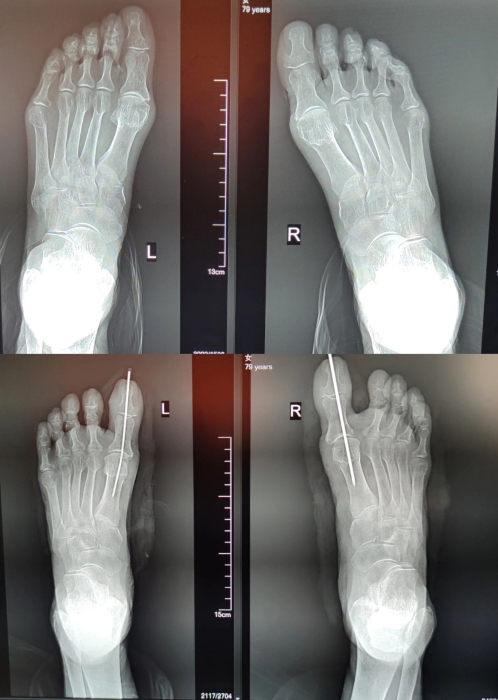

近日(rì),在手麻科(kē)的配合下,骨科(kē)副主任醫師(shī)呂紅(hóng)兵(bīng)憑借精湛的技術(shù),通過術(shù)中實時透視、微創截骨及閉合矯形固定,最終精準矯形,術(shù)後賀奶奶和家屬都(dōu)很滿意。

上/術(shù)前;下/術(shù)後